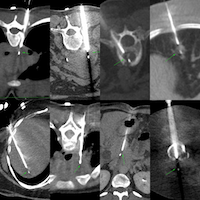

I will be discussing these 5 CT guided biopsy cases from Feb 2026, across different levels of difficulty.

- Description of case

- Pre-test probable diagnosis

- Planning of the biopsy

- How it was done

- Materials used

- Complications if any

- Final diagnosis